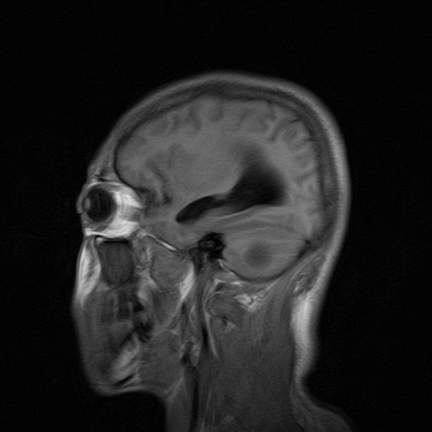

标题: MRI2064:少见病例。男性52,视力下降多年。 [打印本页]

标题: MRI2064:少见病例。男性52,视力下降多年。

四脑室区见混杂信号占位影,脑室系统扩张明显,临近结构显著受压称位,患者52岁,多考虑室管膜瘤可能性大

考虑第四脑室室管膜瘤并梗阻性脑积水;部分性空蝶鞍;左侧上颌窦粘膜下囊肿。

小脑蚓部胶质脑膜瘤突入四脑室;肿瘤内见血管流空信号和钙化信号.

比较典型的脉络丛乳头状瘤并脑积水,鉴别小脑蚓部血管母细胞瘤。